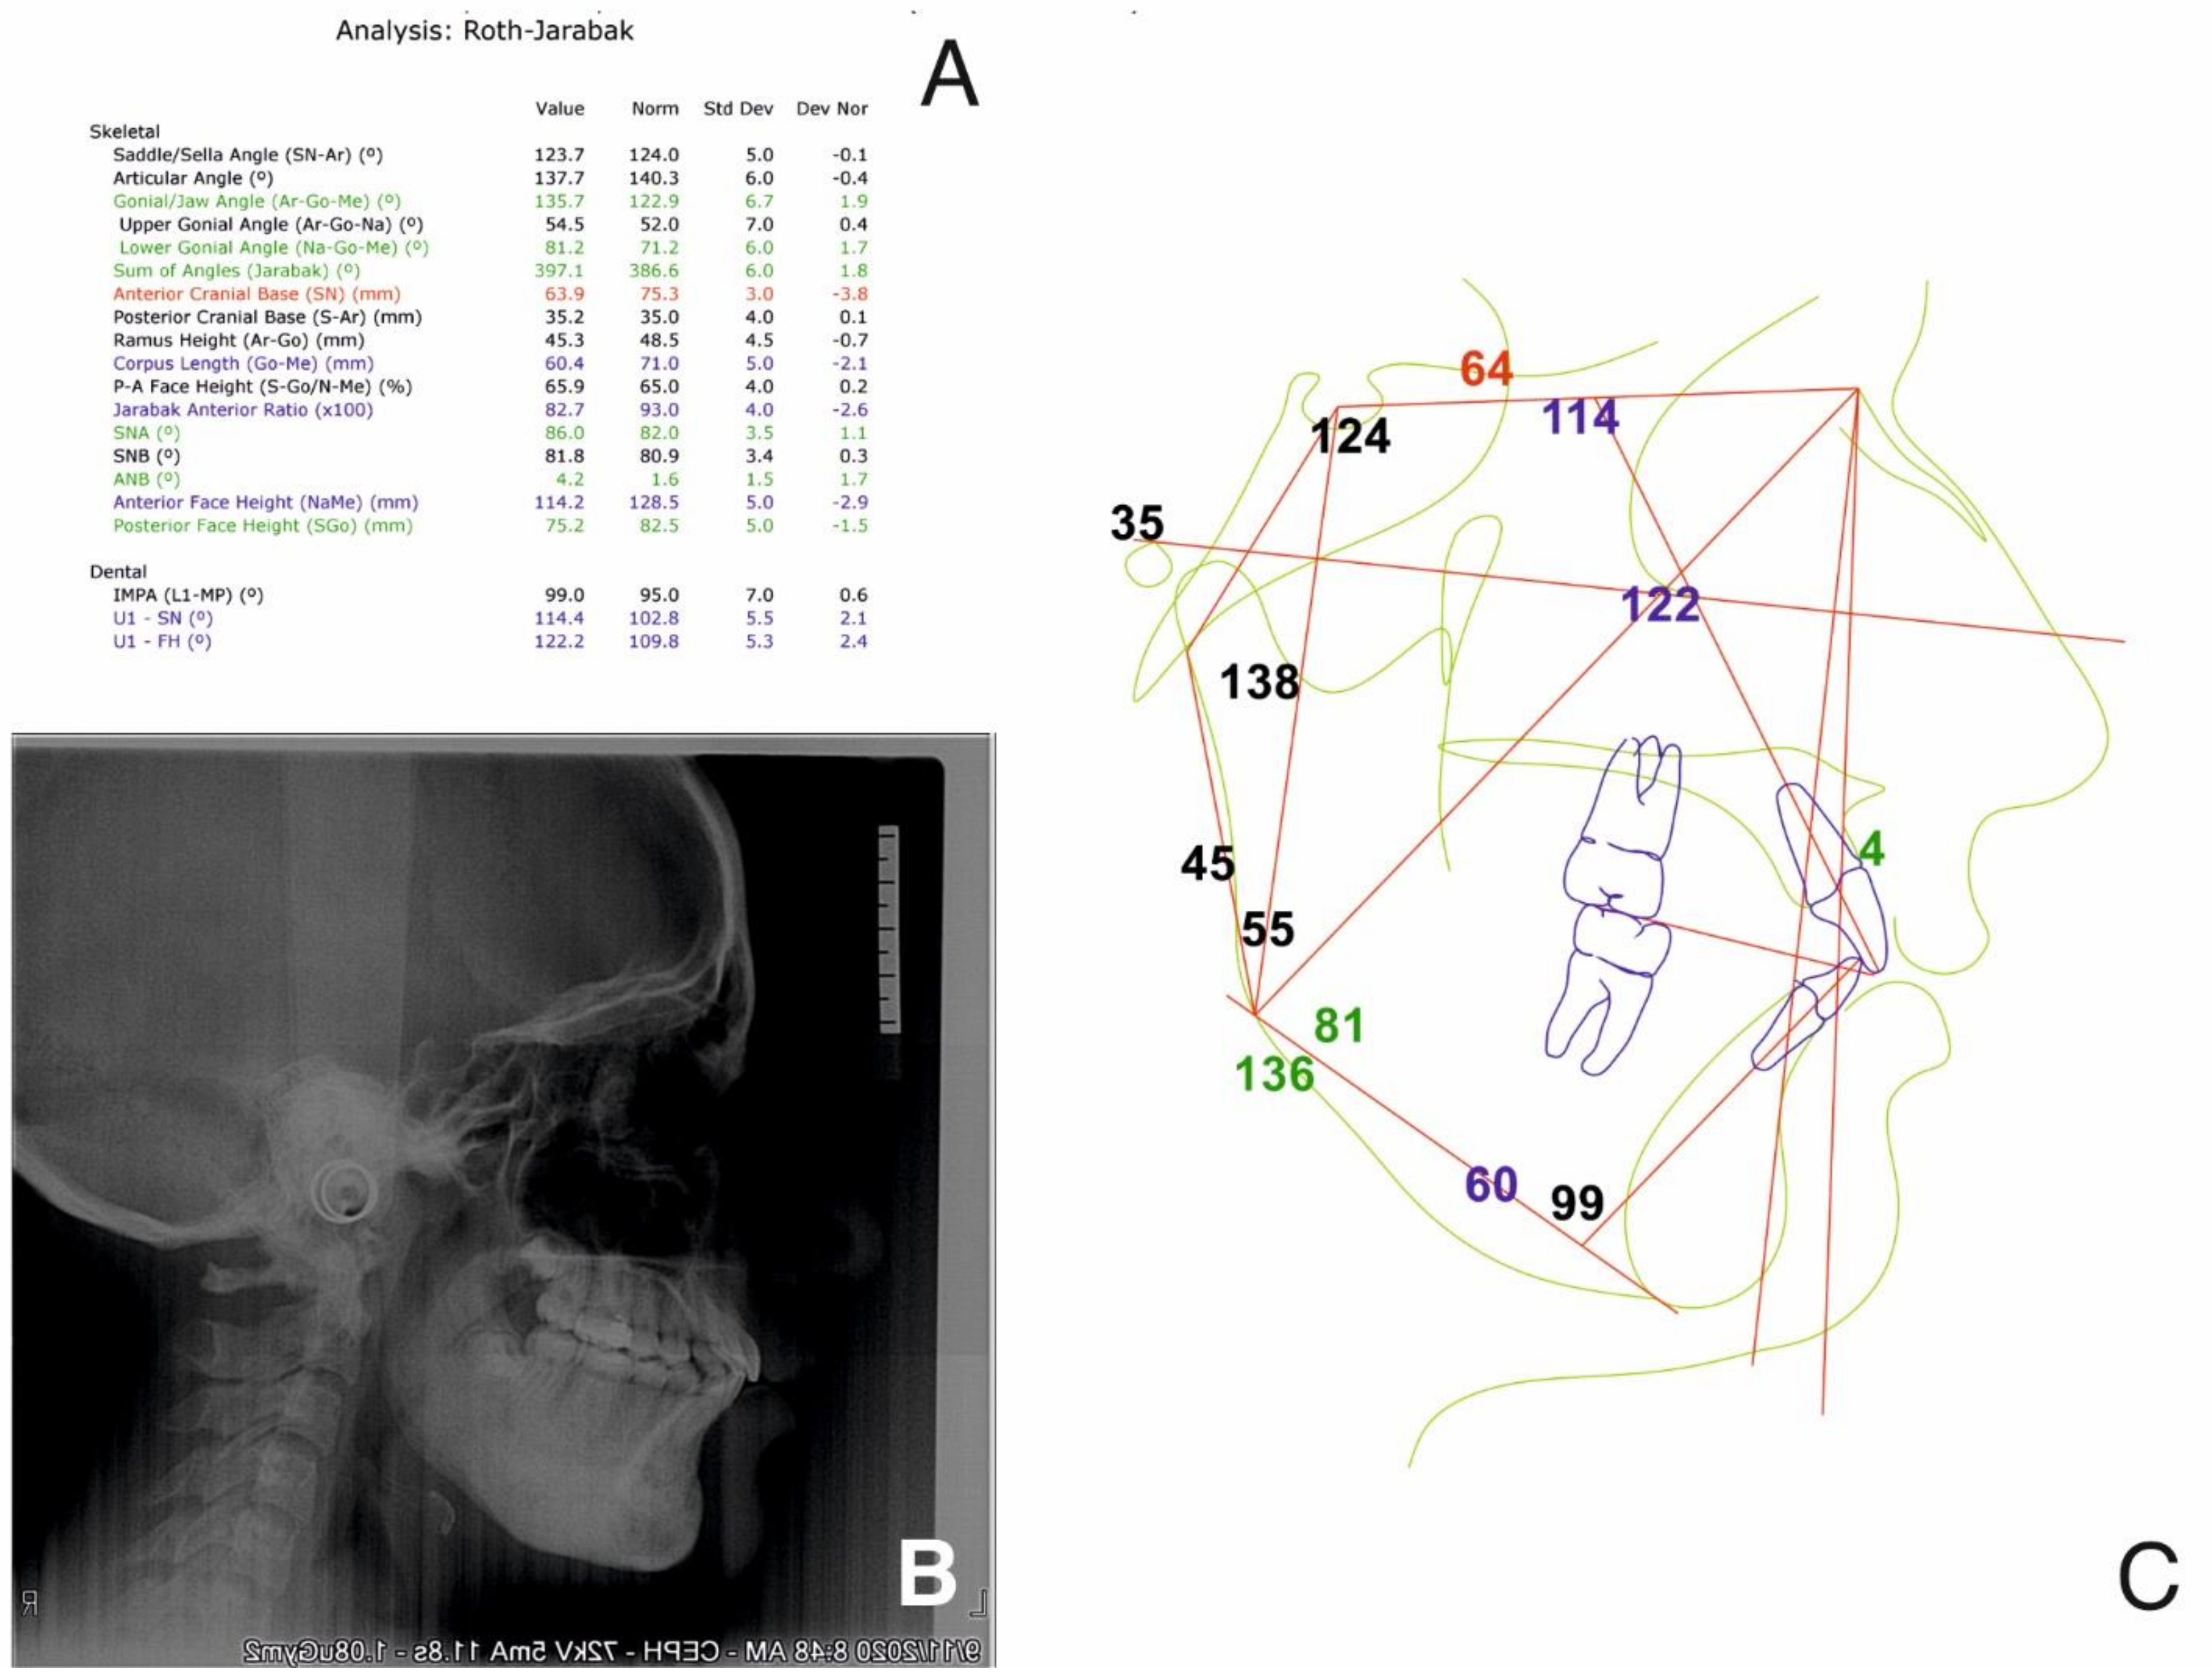

2.2.1. Initial Examination

2.2.2. Treatment Objectives

- Relieve the TMJ pain, stabilize the mandible and muscle relaxation (physiotherapy and splint therapy);

- Orthopedic treatment to ensure a normal growth and development of the maxilla and the mandible, and the correct eruption of the permanent teeth (class I for canine and molar);

- Diminishing the growth of the inferior lower third of the face;

- Limiting the evolution of the osteomyelitis process by preventing further invasive treatment of the patient (braces, skeletal anchorage, any other forces that are beyond physiological which might increase the osteomyelitis process);

- Deconditioning of the tongue trust and nail biting and improving oral hygiene.